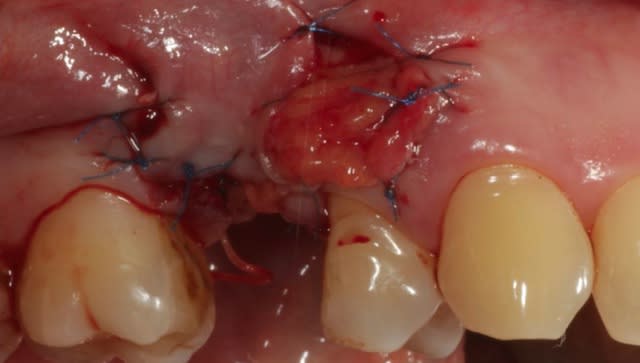

J'ai décidé de réaliser un lambeau déplacé latéralement associé à un conjonctif enfoui le jour de l'extraction afin d'avoir des tissus mous de meilleure qualité pour la greffe, ci joint les photos à 6 semaines.

--

mac